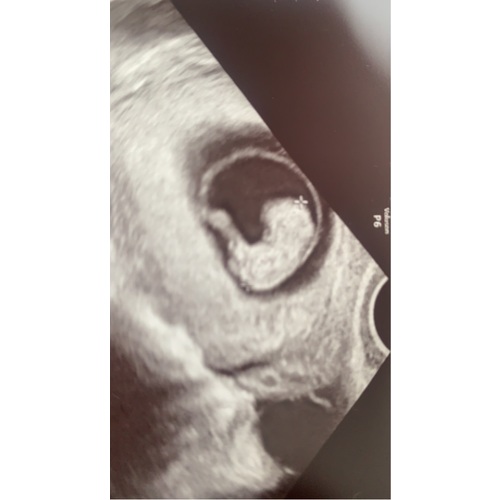

Wil wel nog even pronken met de echofoto ☺️ ik zie een klein gezichtje erin!